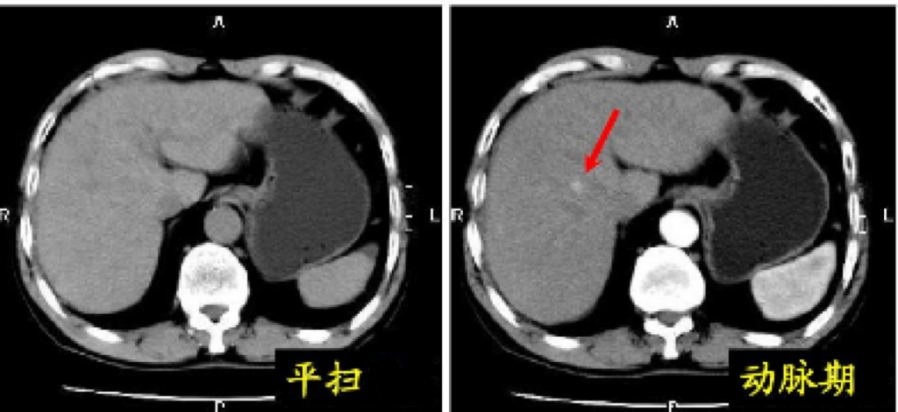

平扫CT是观察病灶的形态、边界和大小等,一般提供观察的信息量比较少。

增强CT是使用对比剂后观察不同时期病变内血供情况,为病变组织与正常组织的对比提供了更多信息,更加有助于疾病的诊断与鉴别诊断。